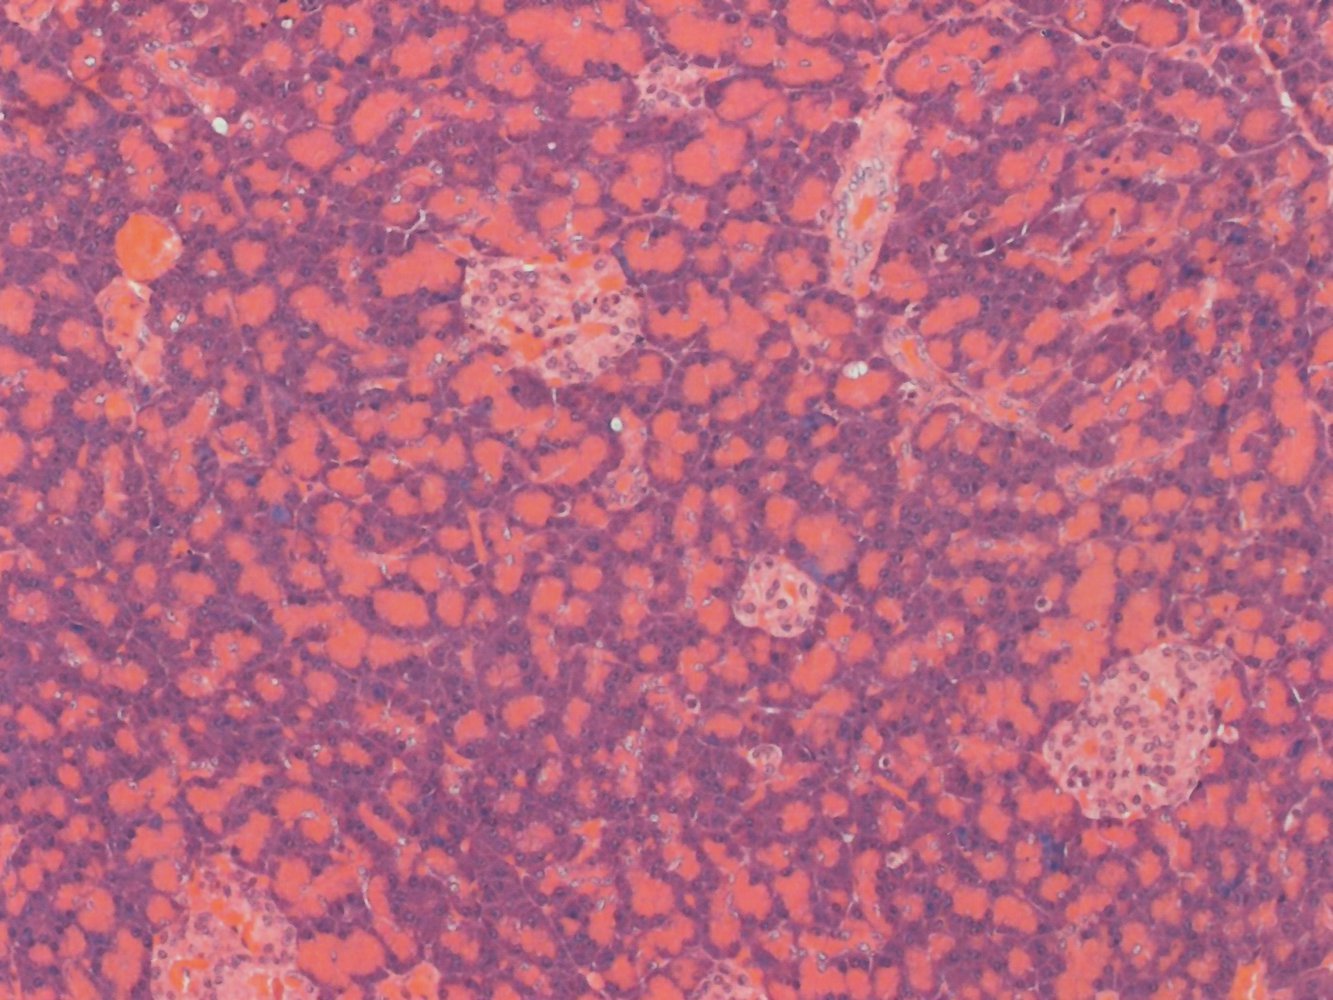

Parenchyma of pancreas

Composed predominantly of deeply staining exocrine acinar cells (example indicated by white dashed outline) and a few scattered islets of Langerhans composed of pale-staining endocrine cells (red overlay). The acinar cells are pyramidal in shape. They have a basophilic base (because of an abundance of rough endoplasmic reticulum) and an eosinophilic apex (because of an abundance of zymogen granules). Centroacinar cells (green overlay; black arrows) are the epithelial cells of the pancreatic ducts and are identifiable as pale-staining cells located centrally within the acini. Centroacinar cells secrete bicarbonate. The Islets of Langerhans are composed of clusters of pale, round endocrine cells that produce insulin, glucagon, and somatostatin.

Pancreatic acini and islets of Langerhans

Pancreatic parenchyma is composed predominantly of deeply staining exocrine acinar cells among which are scattered islets of Langerhans composed of pale-staining endocrine cells. Acinar cells are pyramidal in shape. The base of acinar cells is basophilic (examples indicated by white arrows) because of an abundance of rough endoplasmic reticulum and basally located nuclei. The apex of acinar cells is brightly eosinophilic (examples indicated by white arrowheads) because these cells contain abundant zymogen granules. The endocrine cells of the islets of Langerhans (green overlay) are pale and round and produce insulin, glucagon, and somatostatin.

Parenchyma of the pancreas

The pancreas is encapsulated by a thin connective tissue capsule and surrounded by peripancreatic fat. The pancreatic parenchyma is divided into lobules by connective tissue septae in which lie blood vessels, nerves, and branches of the pancreatic ducts. Each lobule of the pancreas is composed of clusters of dark-staining exocrine acinar cells that contain pancreatic zymogens. Scattered amid the acinar cells are the islets of Langerhans composed of pale-staining endocrine cells that secrete pancreatic hormones. Centroacinar cells are the epithelial cells of the pancreatic ducts and are located at the center of the pancreatic acini. Centroacinar cells secrete bicarbonate.